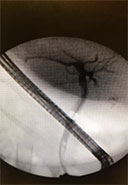

A 51-year-old female underwent a laparoscopic cholecystectomy for symptomatic cholelithiasis. Her postoperative course was complicated by intermittent upper abdominal symptoms for a few months, with a severe attack four months later that prompted admission and further workup. The patient was found to have obstructive jaundice and elevated LFTs (total bilirubin 2.6, direct bilirubin 1.6, alkaline phosphate 584, ALT 427 and AST 110). Furthermore, an MRCP suggested a large ovoid filling-defect in the distal CBD (Figures 1 and 2). Gastroenterology consult was placed for further management.

Figure 1

An ERCP was performed with the use of a Dreamtome™ RX Cannulating Sphincterotome and guidewire cannulation. The cholangiogram revealed a dilated duct, and a definitive large ovoid filling-defect in the distal CBD. Prior cholecystectomy clips were intact with no signs of extravasation to suggest any leak. A large biliary sphincterotomy was performed with copious bile flow. Then, a SpyScope™ DS Catheter was exchanged and advanced into the biliary tree to the bifurcation of the hepatics. Surprisingly, the distal CBD actually showed a mass effect, with marked irregular, hypervascular and inflammatory mucosa. Direct biopsies were taken using SpyBite™ Biopsy Forceps (Figure 3). The SpyScope DS Catheter was then slowly withdrawn, and a brief glimpse into the low take-off cystic duct stump showed a filling defect. We then angulated up the stump. Therein, a 3cm stone was visualized, fully-impacted and causing extrinsic compression of the CBD (Figure 4). An EHL probe was then advanced through the SpyScope DS Catheter, and 1,800 shots were administered to the stone with subsequent breakdown into numerous, smaller fragments (Figure 5). A SpyGlass Retrieval Basket was used to extract the majority of the stones into the duodenum (Figure 6). A number of stones refluxed back into the CBD as irrigation was performed throughout the procedure. We then exchanged a 9-12 balloon catheter and swept out the residual stones. The final occlusion cholangiogram revealed no further filling-defects.